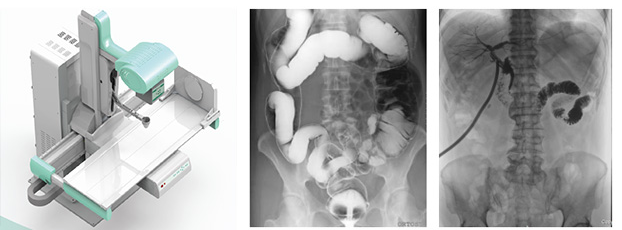

近年來,DR設備正朝著更加準確化、輕便化、智能化和多維化方向發展,出現了多功能動態DR、移動DR、三維化DR產品等等。其中多功能動態DR大大提高了普通放射設備準確診斷的能力,為臨床創造了價值。接下來給大家分析下多功能動態DR是如何提高工作效率的。以下是部分體位介紹及解決方案:

在這些對球管中心線和受檢部位形成角度有要求的體位的擺位過程中,可以應用多功能動態DR的電動控制擺臂、數字顯示角度值和動態透視影像觀察功能等特性,使這些體位的擺位更加準確、讓醫生工作效率更高!如果您想采購普愛醫療的多功能動態DR,或了解產品技術參數,歡迎聯系我們。